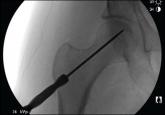

Intraoperative Fat Embolism During Core Decompression and Bone Grafting for Osteonecrosis of the Hip: Report of 3 Cases and Literature Review

Osteonecrosis (ON) of the femoral head, without timely intervention, often progresses to debilitating hip arthritis. Core decompression (CD) with...